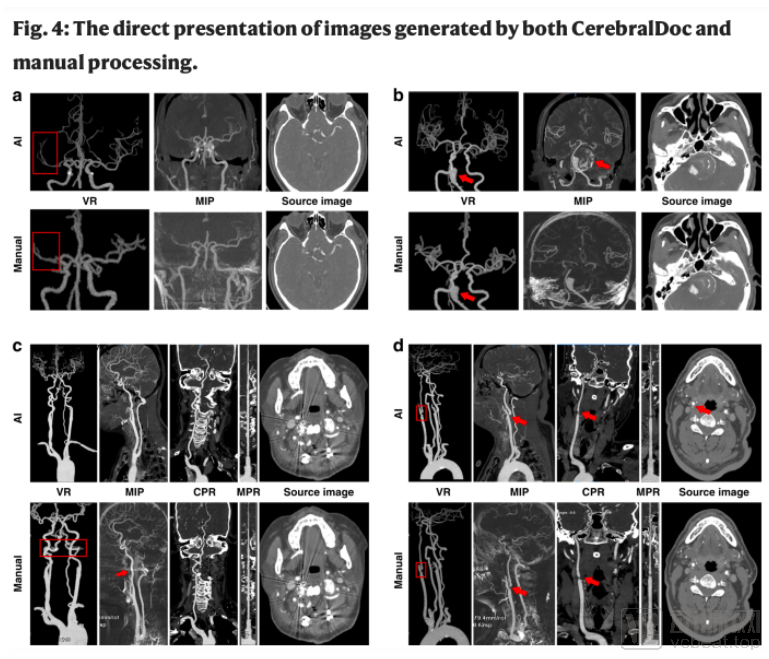

a右脑中动脉闭塞,没有建立侧支循环;b基底动脉瘤伴血栓和钙化,可在CerebralDoc重建的MIP中观察到;c寰枕手术后,AI中的金属伪影得到了更好的抑制;d直接由主动脉引起的右颈总动脉和左椎动脉的分叉严重狭窄